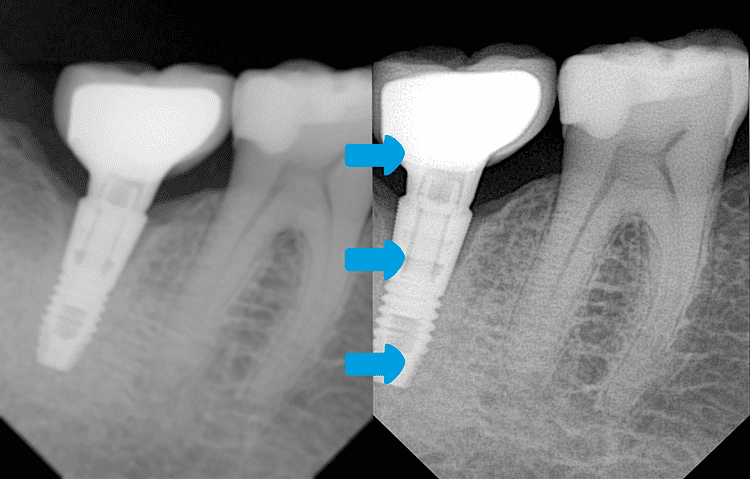

Algoritmo de Mejora de Nitidez para Radiografía Periapical

Precisión revolucionaria para diagnósticos dentales impecables Descubre un avance trascendental en imagenología dental.

Nuestro inteligente algoritmo de mejora de nitidez —desarrollado específicamente para radiografía periapical— ofrece una claridad diagnóstica sin precedentes mediante procesamiento de imágenes de alto rendimiento.

- Mayor claridad y precisión para diagnósticos exactos

- Reducción de borrosidad y artefactos — incluso en anatomías complejas

- Revelando lo invisible – Redefiniendo el diagnóstico de precisión